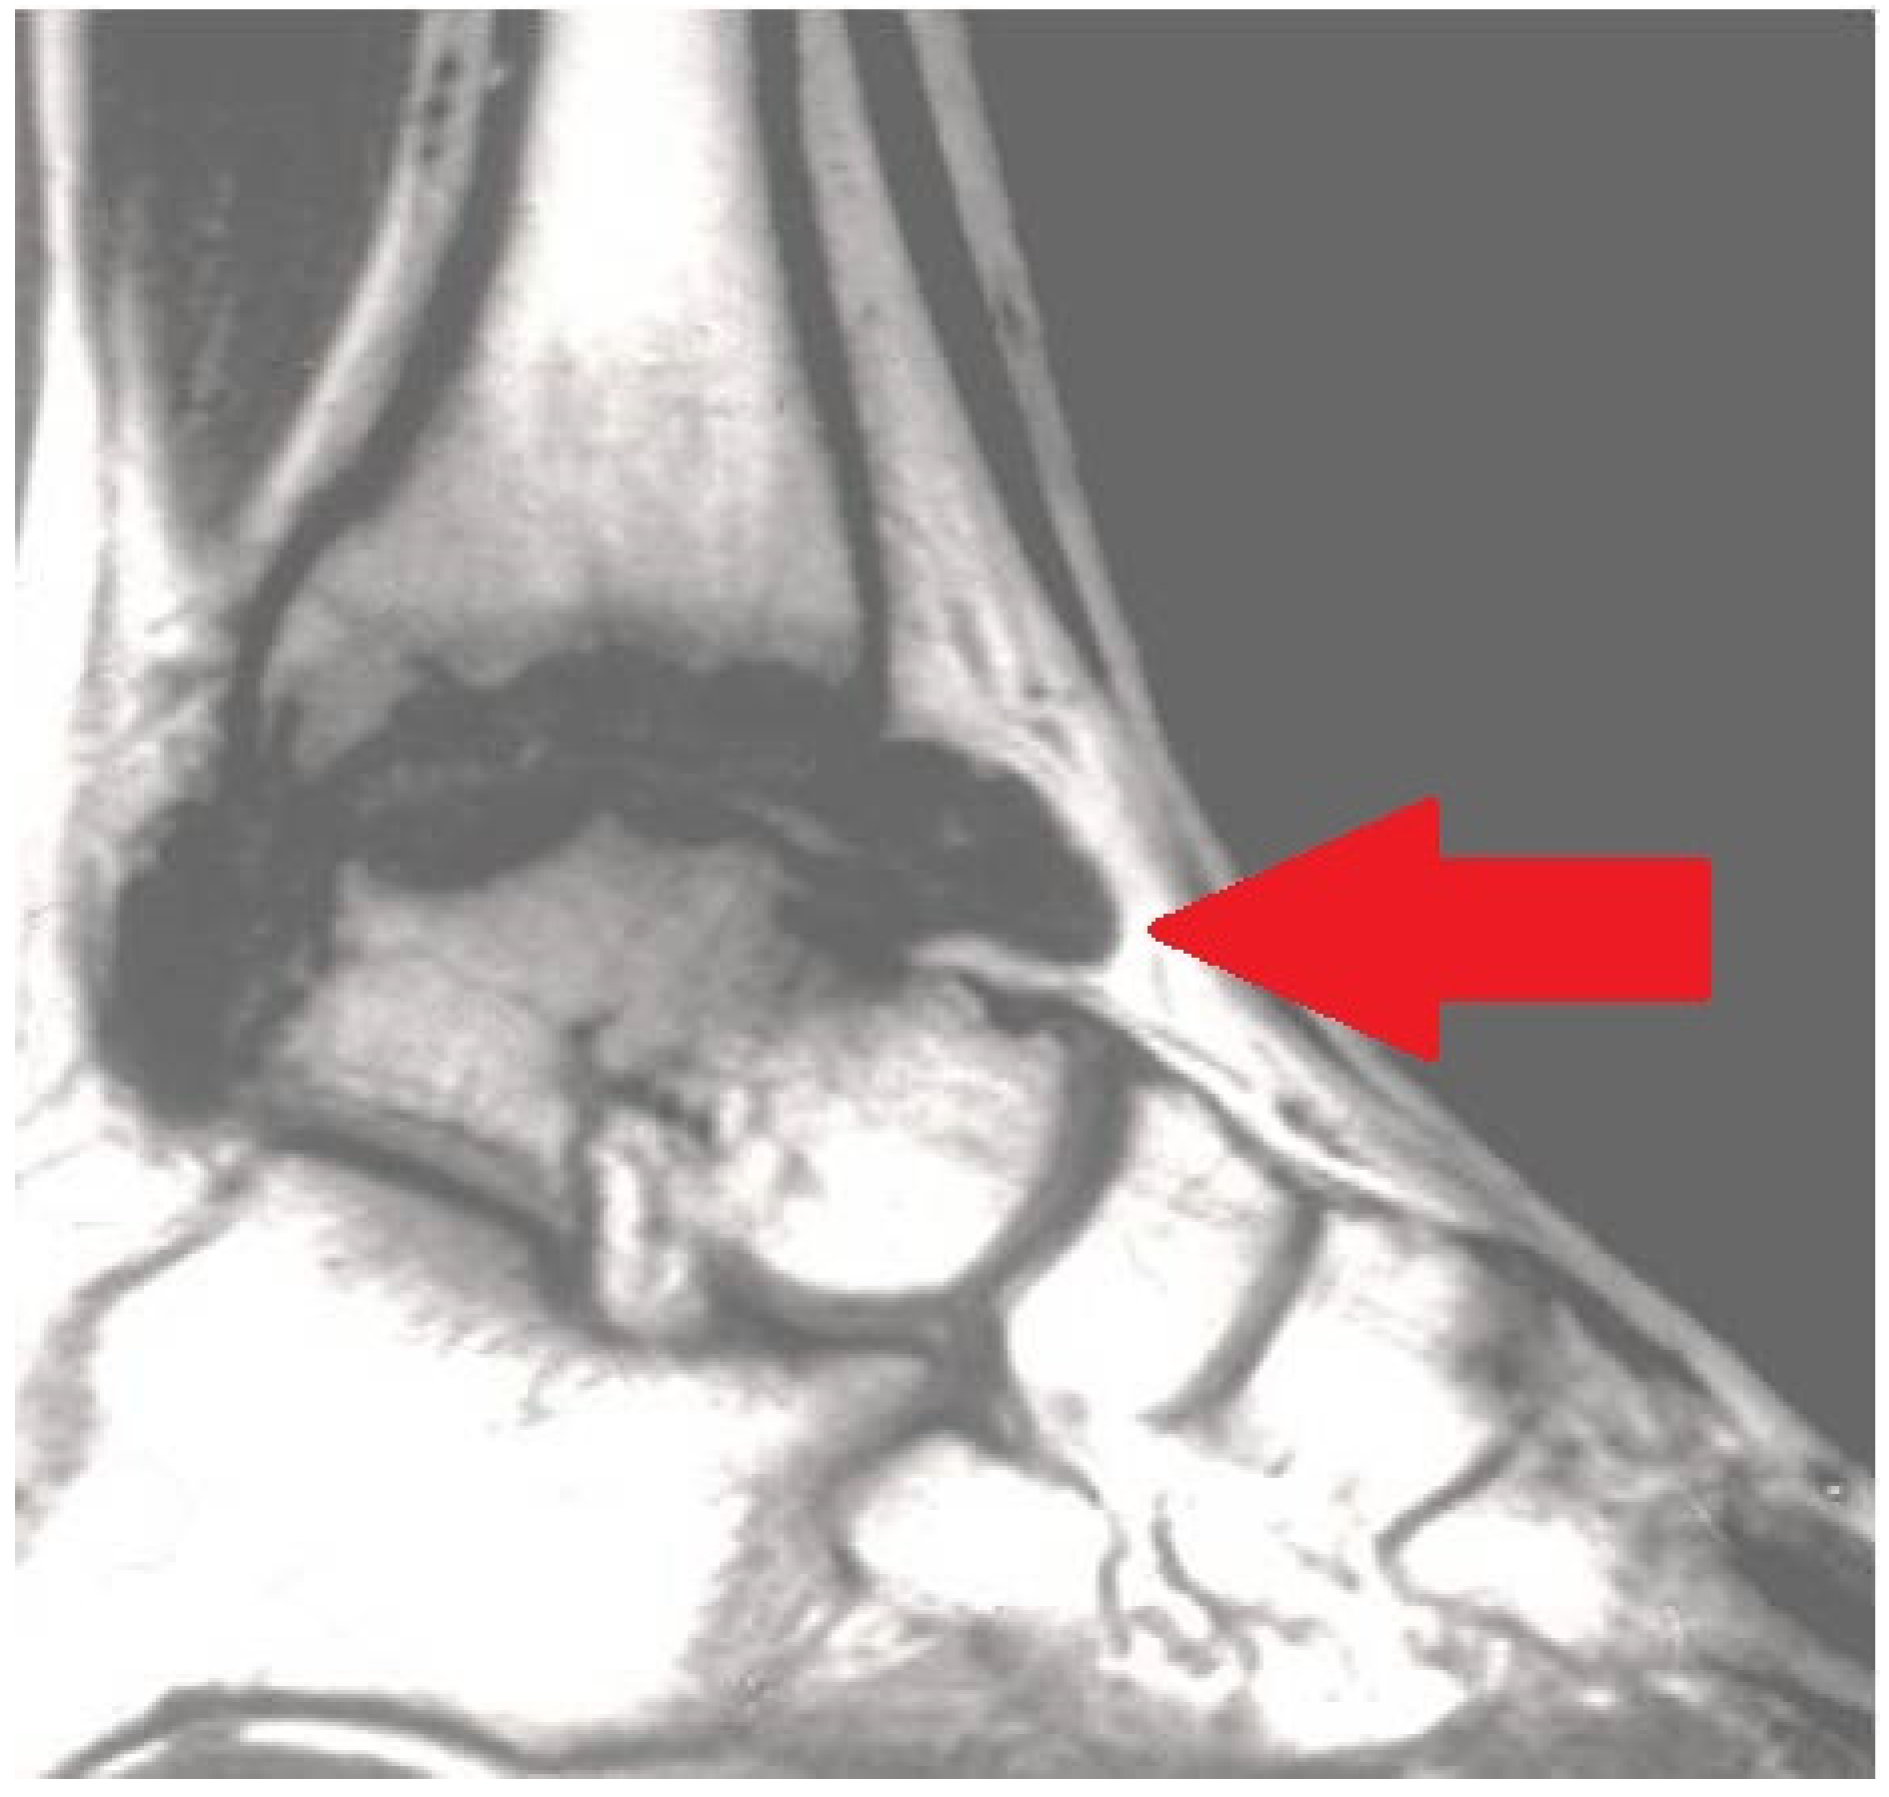

Figure 3.

Magnetic resonance imaging (MRI) exhibiting serious chronic hemophilic synovitis (CHS) of the ankle (arrow).